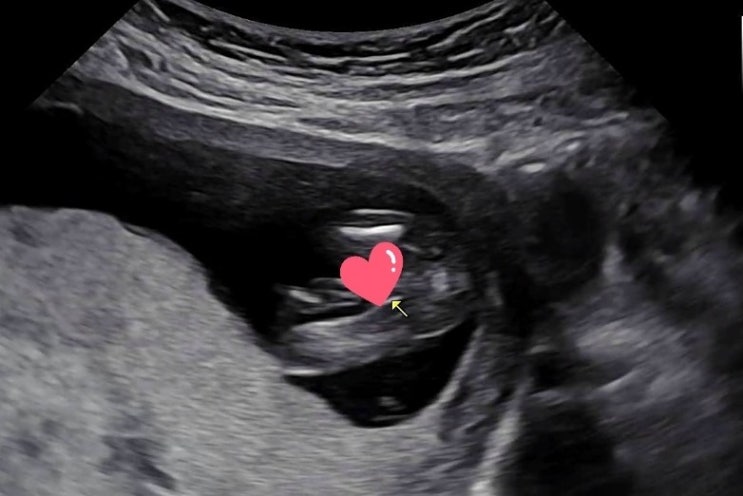

임신 20주차 깜짝 파티 베이비샤워

이제 21주차가 되었습니다아 주말에 친한친구들과 그리고 제남편, 친구 한명 남편까지 6명이 서울 근교 남...

임신 중기 14주 15주 16주 성별 확인 영양제 바꾸기

벚꽃놀이 잘 다녀 오셨나요? 이번 봄은 살짝 늦게 찾아와준 것 같아요 그래도 4월 되고 따뜻한 봄을 잘 즐...